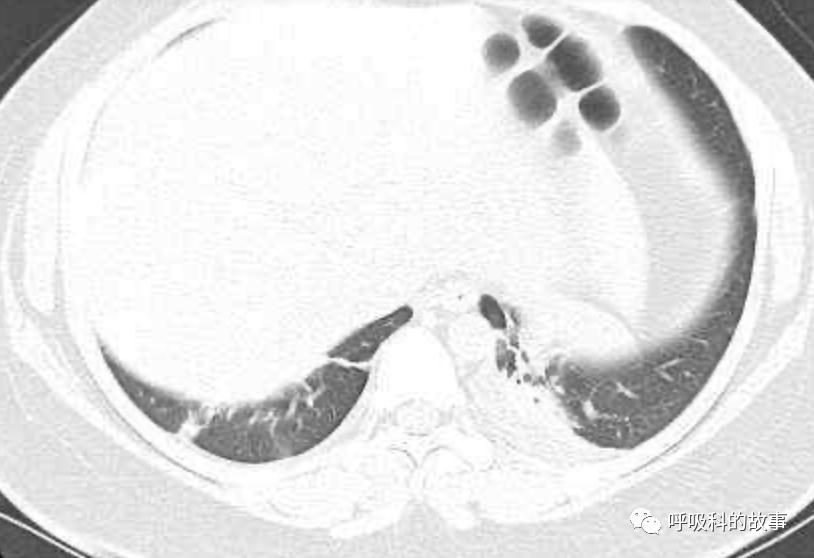

患者发热后行胸部CT检查(6月21日,住院第13天),可见两下肺有条片影,当时考虑是肺炎引起的发热。

可是在6月26日(往院第18天)仍持续发热的情况下复查肺部CT,肺部病灶已明显吸收了。那么患者发热的原因到底是什么呢?为什么患者高热的情况下血白细胞不升反降,C反应蛋白也没有明显增高?这个时候消化科医生也迷茫了,这可怎么办?于是请感染科和呼吸科医生一起会诊,共商计策。